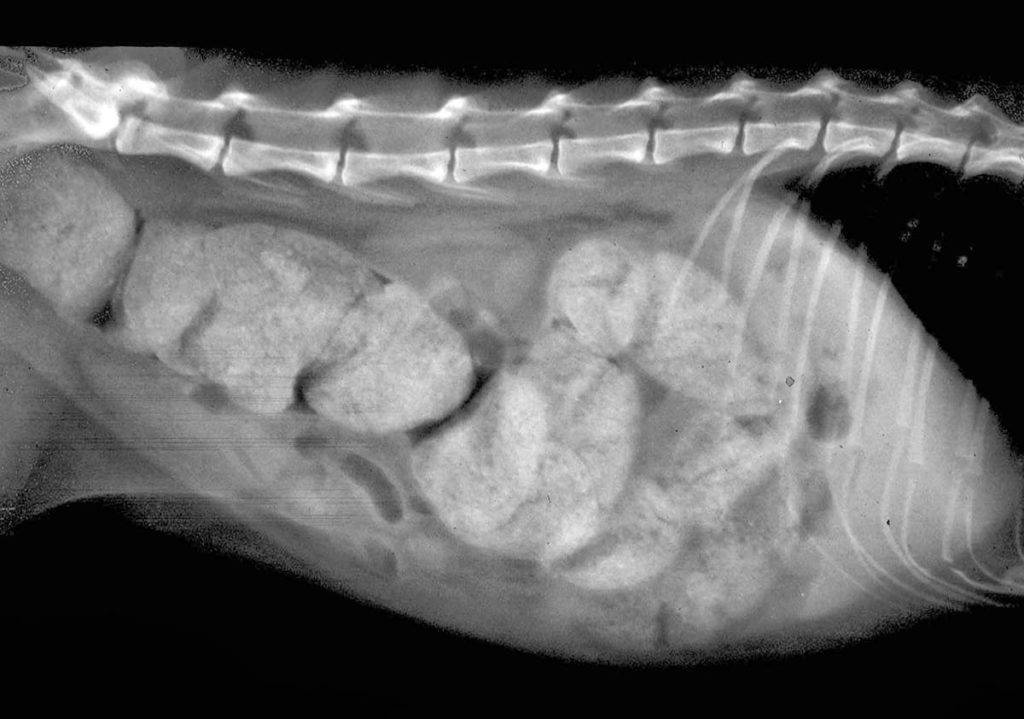

Если кот не ходит какать ни на третий, ни на четвертый день и при этом ведет себя очень беспокойно, возможно, у него не просто запор, а мегаколон. Это опасное состояние, которое можно диагностировать только в клинике. При продолжительном запоре в кишечнике скапливаются сухие и твердые каловые массы.

Они не могут продвигаться к выходу и полностью закупоривают просвет кишки.

При длительном запоре кот отказывается от еды, выглядит вялым, у него начинается рвота. Если обнаружены такие симптомы, лечение нужно начать немедленно, но сначала ветеринар должен убедиться, что речь идет именно о мегаколоне. Придется сделать рентген брюшной полости или УЗИ.

Если диагноз подтвердится, понадобится хирургическое вмешательство, так как медикаментозное лечение малоэффективно.

Окончательный диагноз о закупорке кишечника или его завороте ставится только после проведения рентгенографии с контрастом. Обычно в качестве контраста используют барий, который светится на рентгеновских снимках. По свечению на снимке можно увидеть в каком фрагменте кишечника начинается непроходимость и насколько она серьезна.